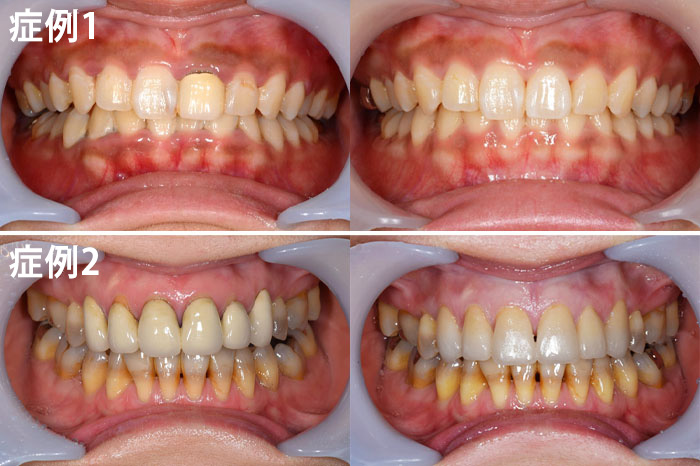

ジルコニアボンドクラウン

| 年齢 | 症例1 20代・女性 |

|---|---|

| 主訴 | 前歯の色が気になる |

| 治療内容 | 左上1の前装冠を除去し、ジルコニアボンドクラウンを入れた。 |

| 治療費 | 165,000円(税込) |

| 治療期間 | 1ヶ月 |

| リスク・副作用 | こちらは神経のない歯に対して行いましたが、神経のある歯では冷たいものがしみるといった症状が出る可能性があります。 また、歯の色ですが、天然の歯に似せて作りますが、全く同じというわけではありませんのでご了承ください。 |

| 年齢 | 症例2 40代・女性 |

| 主訴 | 前歯を10年以上前に入れたが色が気になるので、変えたい |

| 治療内容 | 上顎右側犬歯から上顎左側犬歯までの6本のメタルボンドクラウン除去しジルコニアボンドクラウンを新製しました。 |

| 治療費 | ジルコニアボンドクラウン: 合計990,000円(税込) (165,000円×6本) |

| リスク・副作用 | こちらは神経のない歯に対して行いましたが、神経のある歯では冷たいものがしみるといった症状が出る可能性があります。 また、歯の色ですが、天然の歯に似せて作りますが、全く同じというわけではありませんのでご了承ください。また、以前つけていた被せ物と形が異なることがあります。 |